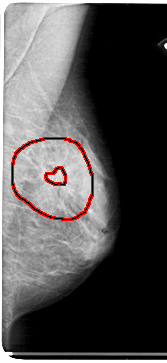

A_1835_1.RIGHT_CC

FILE: A_1835_1.RIGHT_CC.OVERLAY

TOTAL_ABNORMALITIES 1

ABNORMALITY 1

LESION_TYPE MASS SHAPE ARCHITECTURAL_DISTORTION MARGINS SPICULATED

ASSESSMENT 4

SUBTLETY 4

PATHOLOGY BENIGN

TOTAL_OUTLINES 2

BOUNDARY

CORE